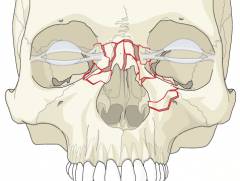

В зависимости от поврежденных костей:

- перелом носовых костей;

- перелом перегородки носа;

- перелом отростков лобной кости и верхней челюсти.

В зависимости от типа поврежденных костей:

- перелом костей носа;

- перелом носовых отростков лобной кости и верхней челюсти.